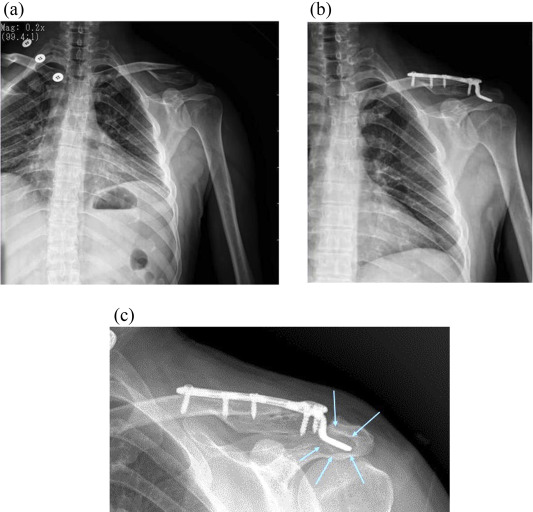

Fig. 2

Fig. 2.

Anteroposterior radiograph of a fully united Neer type 2 distal clavicle fracture with a four-hole hook plate failure (blue arrow) after 6 months which required implant removal (For interpretation of the references to colour in this figure legend, the reader is referred to the web version of this article).